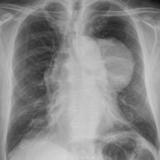

Case 8a Thymoma PA

Date: 03/27/2009

Views: 9449